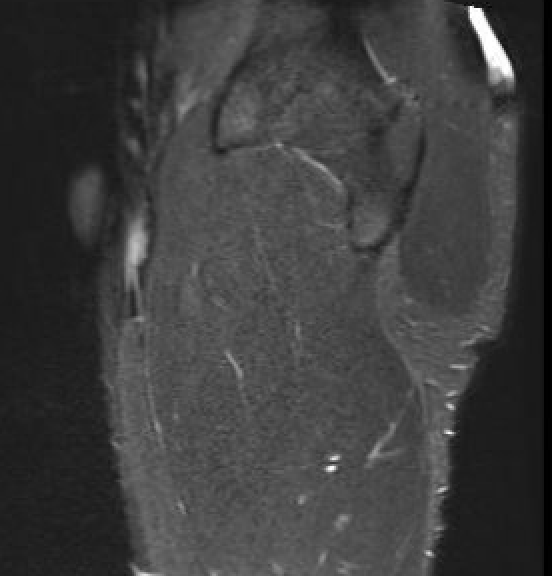

Grade 2B proximal rectus femoris muscle

Grade 3B proximal rectus femoris muscle